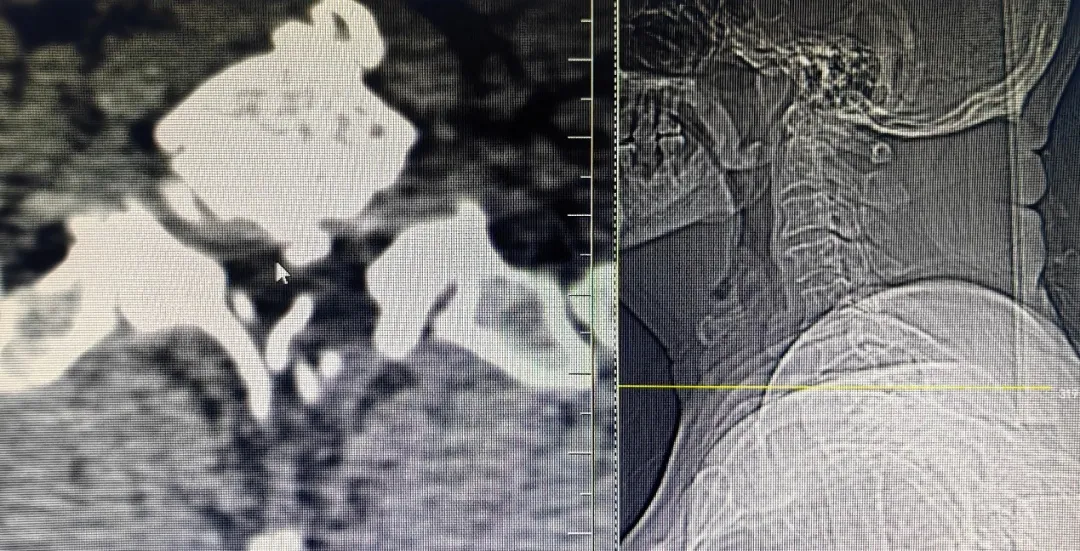

上图为术后复查CT

可见神经根管较术前变宽